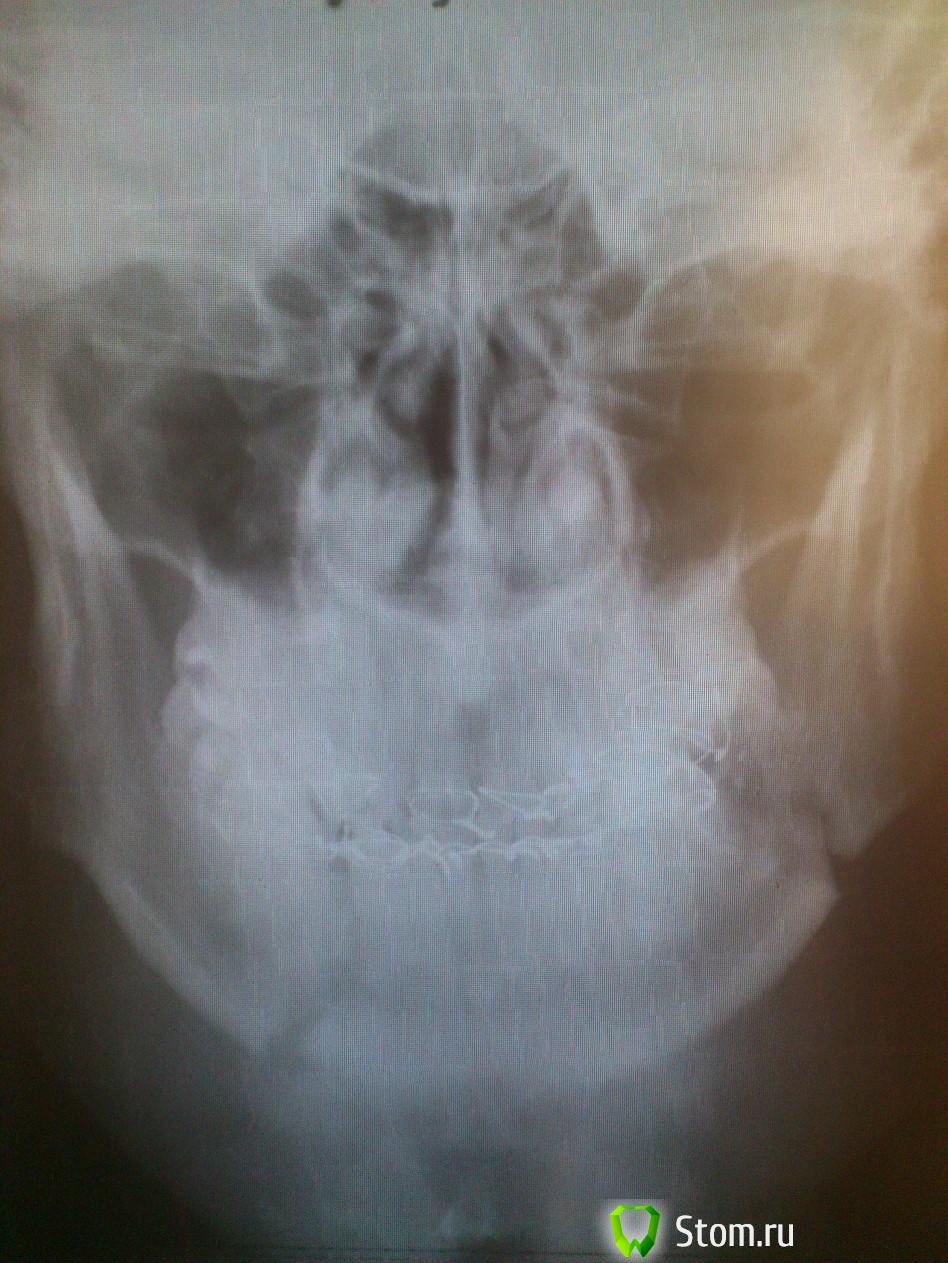

физрук Опубликовано 3 марта, 2012 Поделиться Опубликовано 3 марта, 2012 (изменено) Я сделал снимки через две недели после снятия шин!!Что можете сказать по ним??был перелом в углу нижней челюсти и в области подбородка!! Изменено 3 марта, 2012 пользователем физрук Ссылка на комментарий

kriokov Опубликовано 3 мая, 2012 Поделиться Опубликовано 3 мая, 2012 1. эмаль зубов на месте, ее шинами трудно угробить, после шин бывает повышенная чувствительность зубов, это пройдет. Пасту зубную купите для зубов с повышенной чувствительностью, и к стоматологу терапевту, он проф гигиену проведет2. смещения нет, по этому снимку, прикус скорее всего нормализуется3. Зуб из линии перелома НАДО УДАЛИТЬ, по срокам со стоматологом хирургом определяйтесь.4. болевые ощущения в линии перелома после жевания в течении месяца двух бывают, это нормально, 5. линия перелома у Вас одна, а не две, не переживайте ,просто часто обычный перелом выглядет на снимке в виде двух линий. 1 Ссылка на комментарий